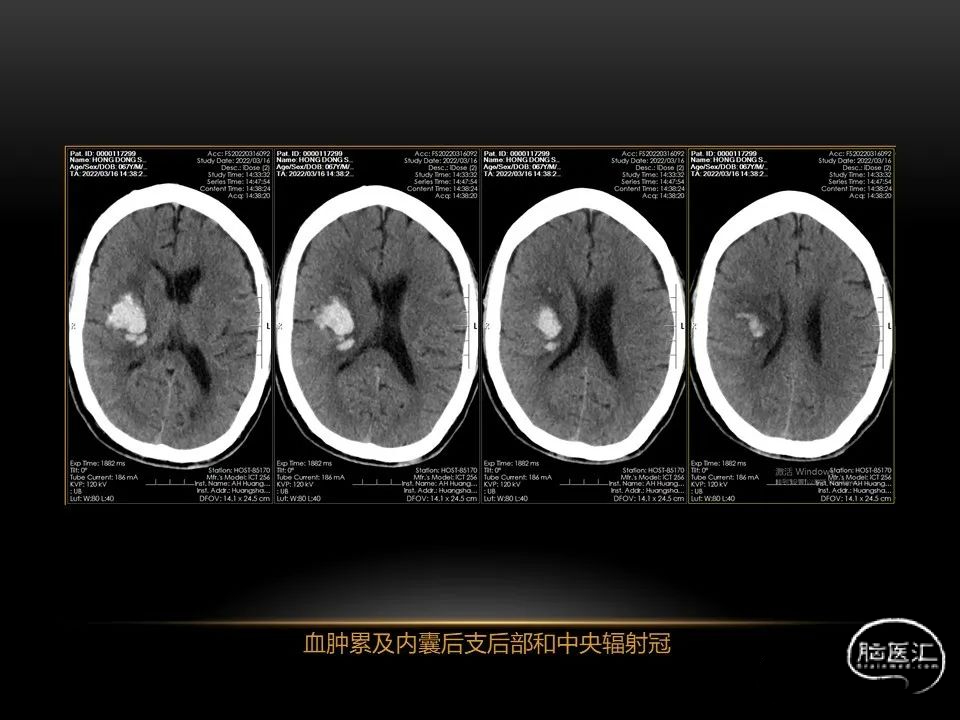

自发性脑出血不仅仅累及内囊后肢才会出现偏瘫及偏身感觉障碍,病变累及大脑脚或辐射冠同样有可能有类似症状和体征。内囊、辐射冠、大脑脚等结构之间是延续的,只是不同区域不同名称而已。定位诊断需要对解剖结构概念清晰,读片准确辨认,灵活掌握。